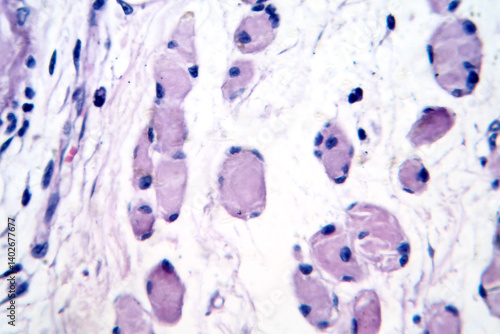

Mikrofotografi - Plakater, Poster, Billeder på lærred